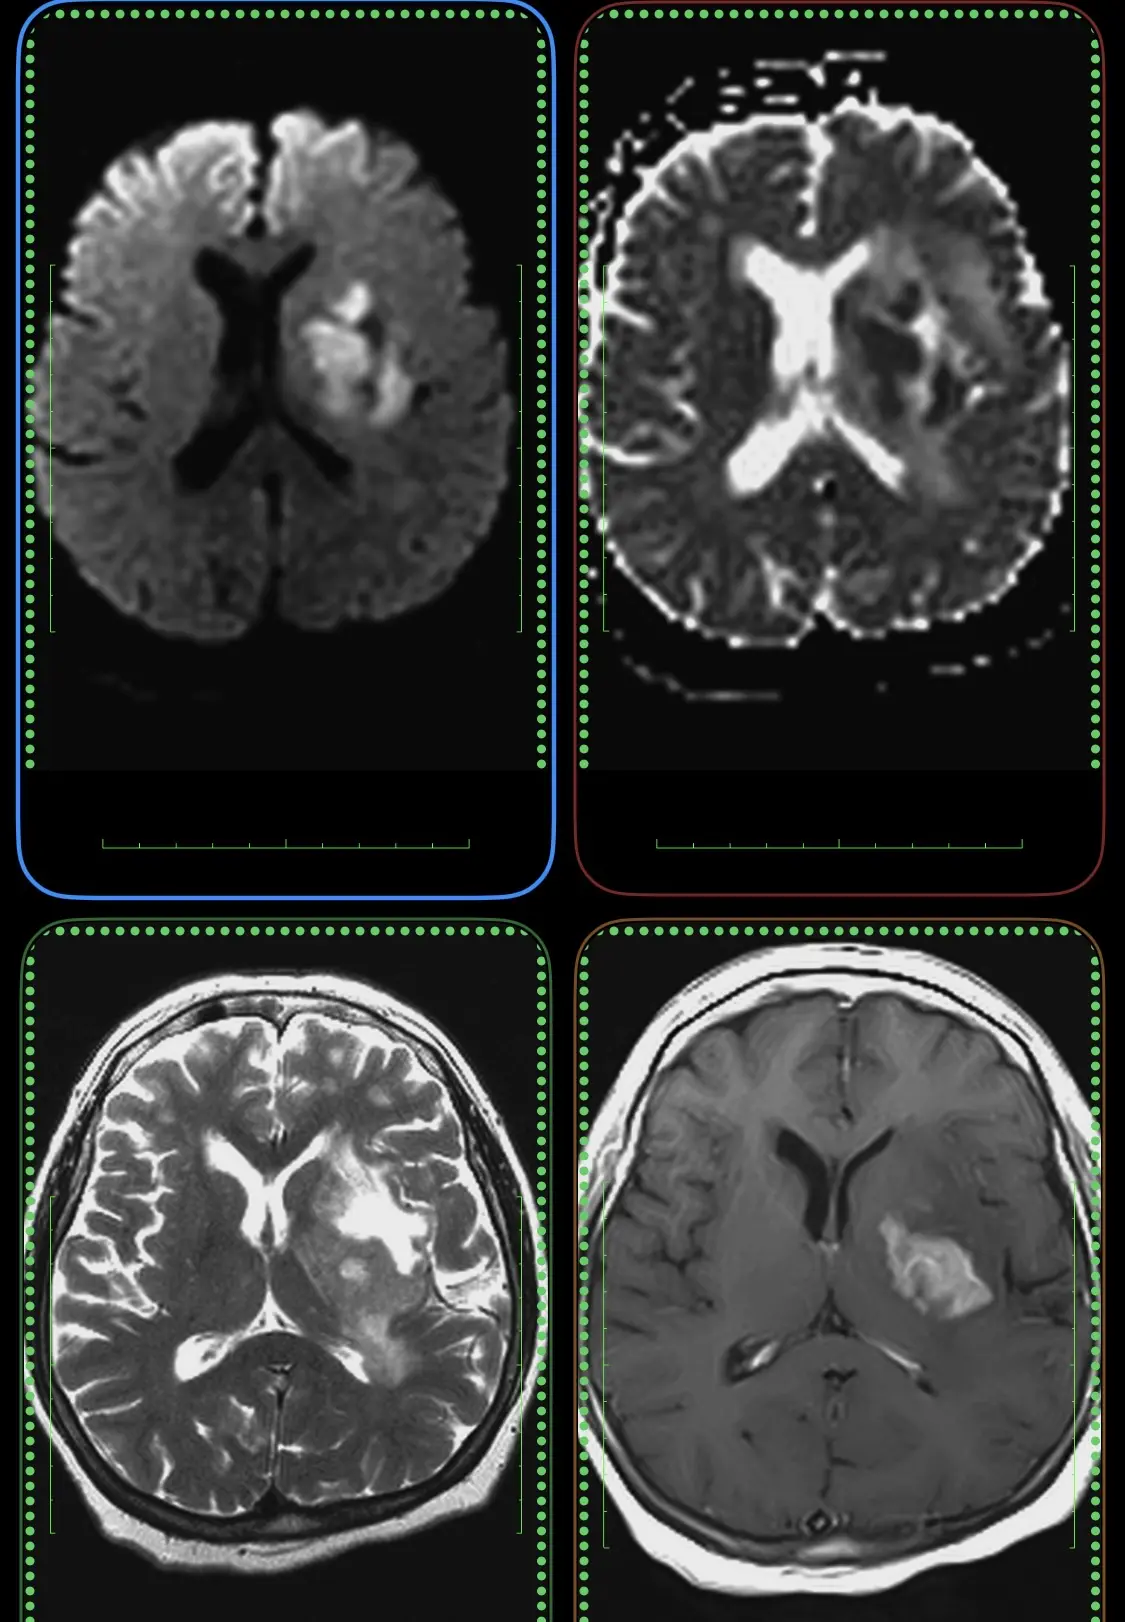

Женщина 32 года. Больной считает себя с 2024 г, когда стала отмечать онемение угла рта. Со слов пациентки ей был предварительно выставлен диагноз - РС, но дополнительных методов обследования и специфического лечения не проводилось. В настоящее время жалоб нет. В исследовании от октября 2024 отмечался очаг в левой затылочной доле с выраженным контрастированием, в настоящее время этот же очаг отмечается с сохраняющимся контрастированием. Формально - есть выполнение критериев диссеминации и в пространстве (юкстакортикальный и перивентрикулярный очаги есть), и во времени (есть усиливающиеся и неусиливающиеся очаги), клиника тоже вполне укладывается. Но! Найти в литературе подобных случаев мне не удалось, видел сам и максимум, что находил в литературе - полгода контрастирования. Получается, мы имеем дело с крайне атипичным рассеянным склерозом, или это не рассеянный склероз. А тогда что? Сосудистая мальформация не вариант - на SWI не видать. Какая-то ганглиоглиома? А другие очаги тогда что? Есть соображения? Кстати, диффузия стойко повышенная, и на б1000 почти не видно (изо). На Т2 не меняется